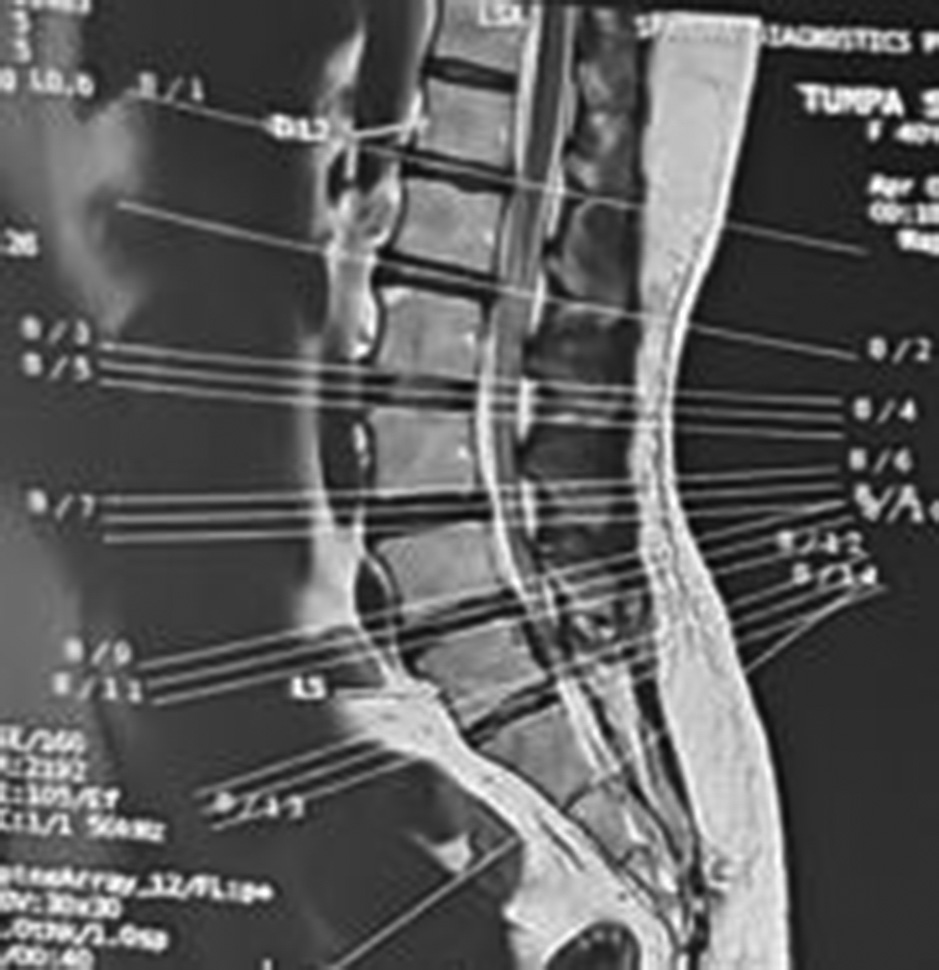

Following spinal anesthesia, patients were positioned prone. A midline incision was made one level above and below the involved segment. C-arm intensifier was utilized, especially when sacralization or lumbarization was identified in preoperative imaging. The spine and laminae were exposed, centering on the affected disc space. Portions of the spinous process and interspinous ligament were excised. The lower halves of both laminae were removed until the epidural fat became visible through the ligamentum flavum in the midline. (Fig. 1). The ligamentum flavum was excised bilaterally, and in certain cases, the overhanging portions of the hypertrophied medial facets were removed using a Kerrison punch. A standard technique was employed for discectomy, ensuring the complete removal of all visible disc material. Both nerve roots were examined for any additional compressive elements before they entered their respective foramina. For L5-S1 disc prolapse, only ligamentum flavectomy was performed with limited laminectomy (even less than the lower half) to facilitate adequate discectomy. The wounds were closed in layers after achieving proper hemostasis. For illustration images from a case of L5-S1 disc prolapsed are presented(pre-operative MRI and post operative X-ray) (Fig. 2-4).

Fig. 2. Sagittal T2-weighted MRI showing L5-S1 disc prolapse